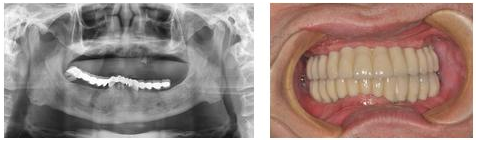

戴牙,进行调试,使咬合达到最佳状态,李大爷对修复效果很满意。

术后效果:

术后追踪:种植牙手术结束后,宁德中富口腔为李大爷制定了跟踪档案。三个月后,医生对李大爷进行回访时,李大爷表示“种植牙真的好,到现在都没副作用或不适感,跟以前自己的真牙差不多,真没想到,现在我终于可以海吃海喝了。”